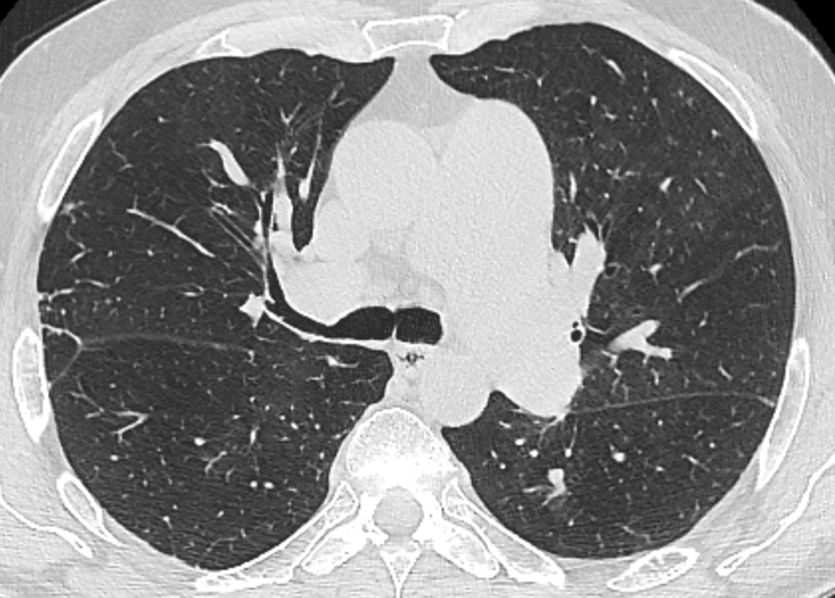

Emphysema is characterized by permanently enlarged airspaces distal to the terminal bronchiole, with destruction of alveolar walls. Emphysema is usually classified according to the part of the acinus predominantly affected. The Computed Tomography appearance of emphysema consists of focal areas or regions of low attenuation, usually without visible walls.

Mosaic attenuation pattern

This pattern appears as patchwork of regions of differing attenuation that may represent (a) patchy interstitial disease, (b) obliterative small airways disease, or (c) occlusive vascular disease. CT features suggesting vascular origin include signs of primary PH, chronic pulmonary embolism, and PVOD.